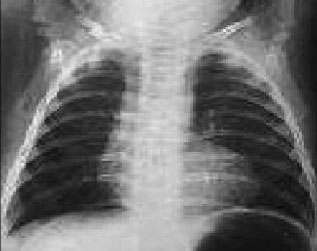

In the child, it is necessary to take into account how the characteristics differ from that of the adult, especially those derived from changes in weight, height and heart rate (PR and QT intervals vary with age).Also, as a child matures, initially the right ventricle is predominant and until 12-14 years there are data of hypertrophy of the right ventricle that are considered normal. The heart rate decreases with age, while the duration of the P wave, the QRS complex, and the PR interval all increase.